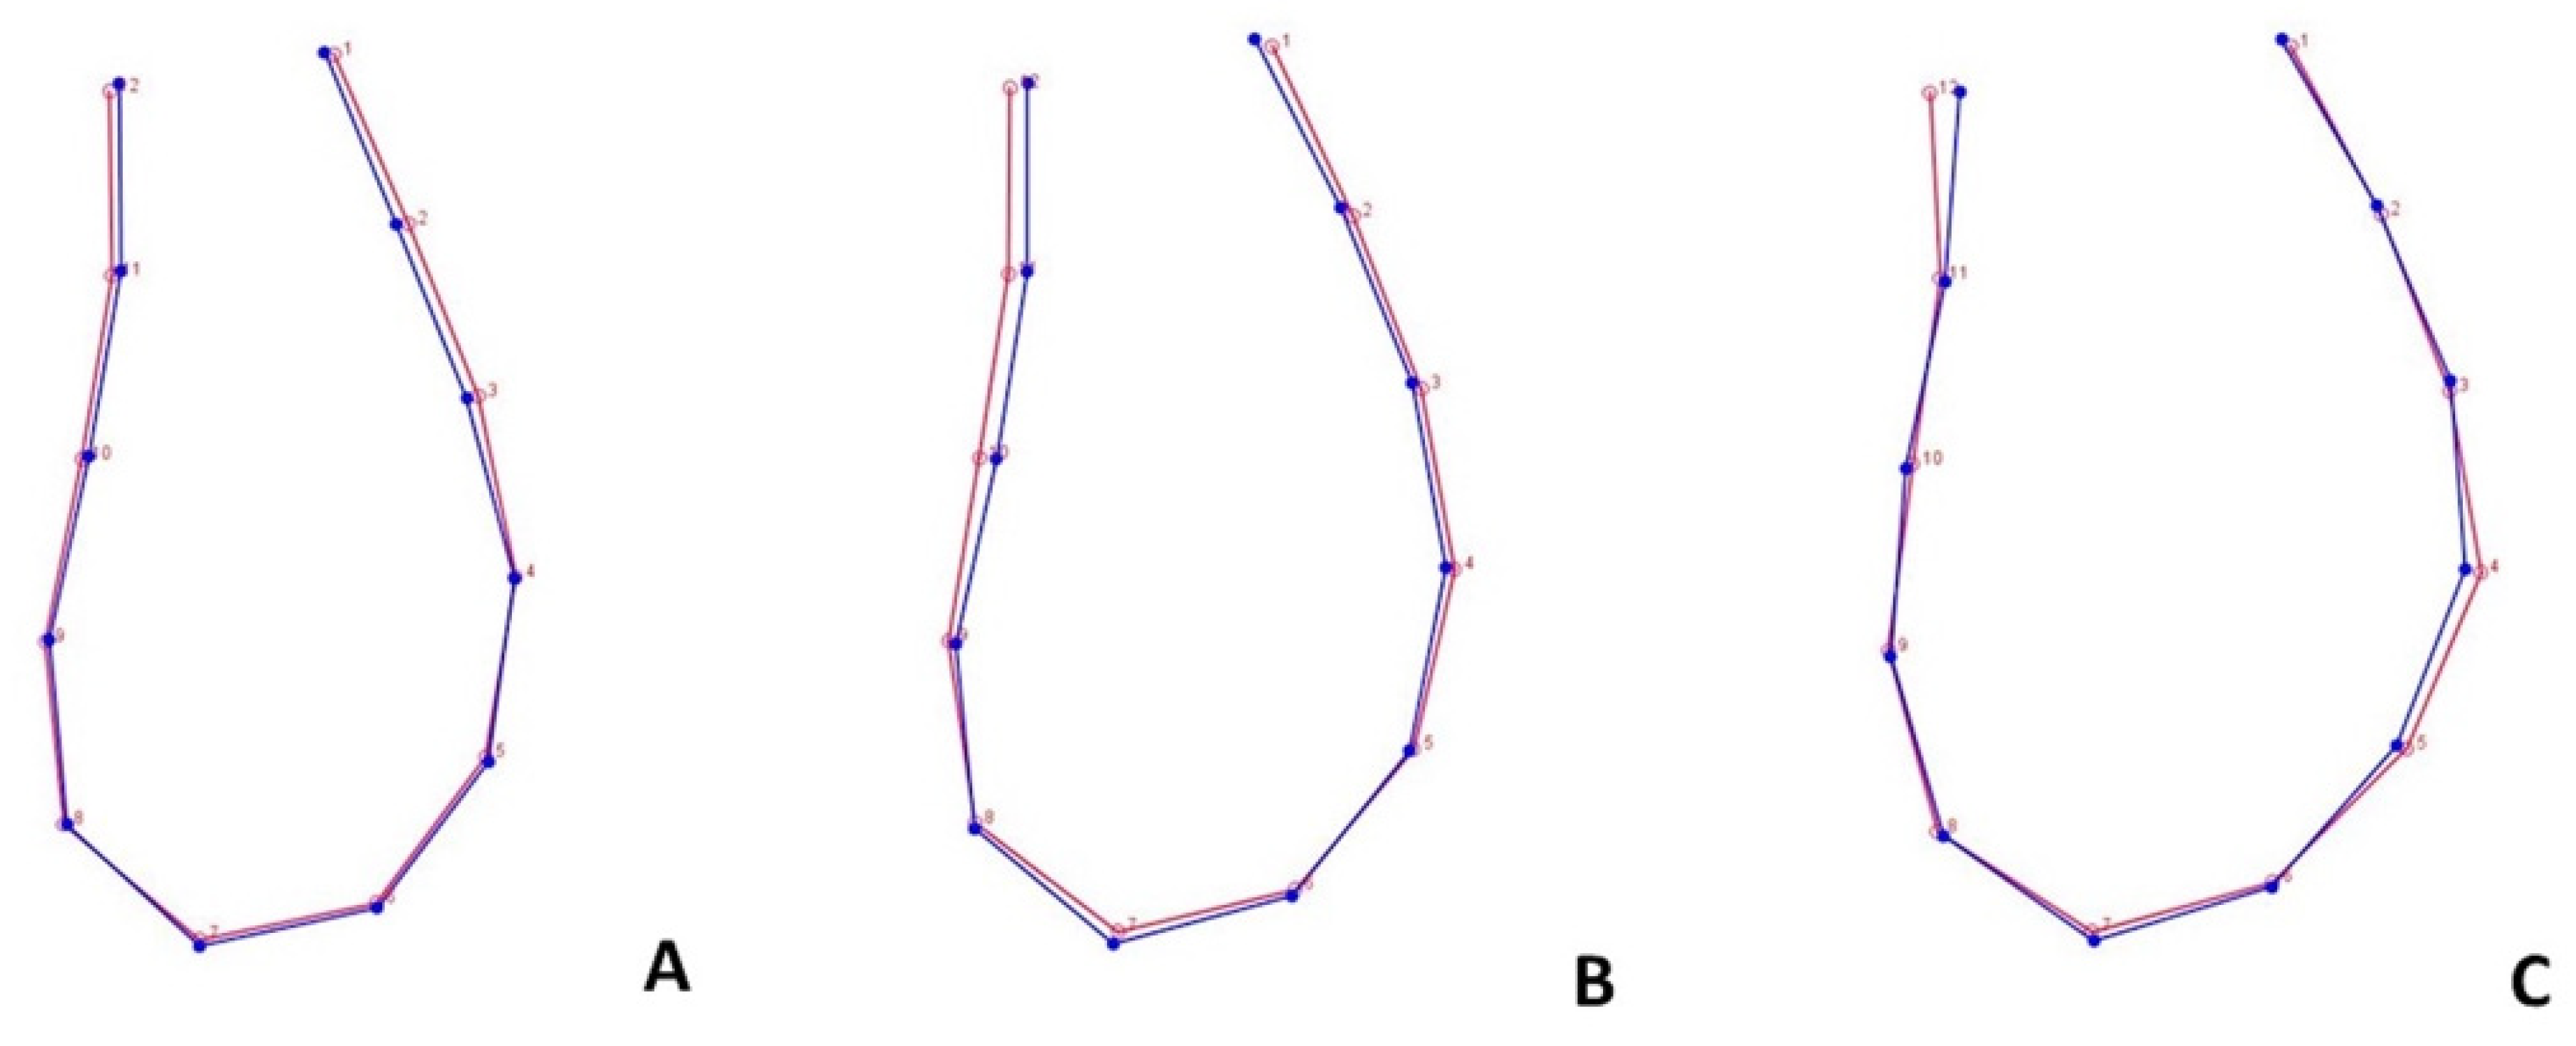

3.3. Form Covariation and Inter-Timing Assessment of Morphological Change

4.3. Ms’Form Covariation and Inter-Timing Assessment of Morphological Change